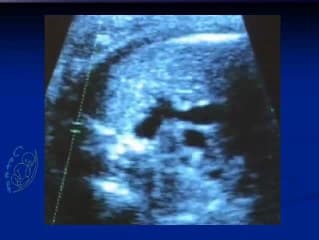

L'auteur chercheur à l'INSERM parle de l'HIFU qui est une technique d'utilisation d'ultrasons focalisée à haute fréquence dont le but est de produire des lésions. Expérimentation chez la guenon avec un monitorage échographique pour visualiser les lésions induites..Quel intérêt en pratique ? Par exemple pour le placenta accreta ou le TRAP !